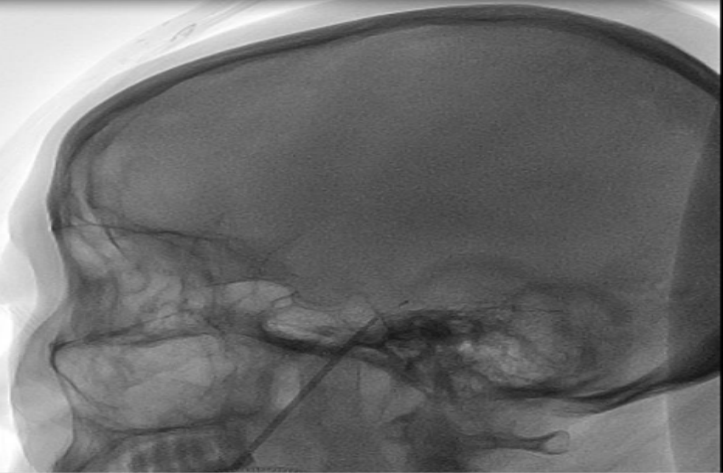

12月20日,在麻醉科、介入手术室的密切配合下,由李想主任手术团队为患者施行PBC术。手术在全麻下进行,术者在患者的患侧(左侧)口角外侧2.5CM 皮肤处穿刺进针,在DSA机器的精准定位下,穿刺针到达左侧半月节并置入球囊,注入造影剂扩张导管末端球囊。通过显影确认球囊位置准确后,压迫数分钟,将穿刺针、球囊导管一并撤出,结束手术。术程顺利,实际不到30分钟即完成手术。术后患者面部疼痛完全消失,疗效立竿见影,达到了“麻醉苏醒即治愈”的效果。